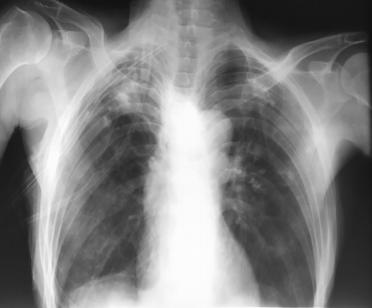

患者70岁,有慢性吸烟史和慢阻肺病史。因“呼吸困难1周”入院。临床检查:脉搏106次/分钟、血压110/78mmHg,呼吸24次/分钟,血氧饱和度90%。气管偏左,右半肺各区域无呼吸音,叩诊音高共振。实验室检查正常,除白细胞增多。胸片检查显示右侧气胸,肺塌陷,气管向左移(图1)。置入右侧ICD,气体排出,患者呼吸困难有所改善。胸片显示塌陷肺复张(图2)。

图2胸片显示ICD置入后气胸